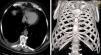

Caso clínicoDescribimos un caso de migración intratorácica de un catéter peritoneal tras derivación ventriculoperitoneal y se revisan las escasas referencias en la literatura, con discusión de los posibles mecanismos de penetración en la cavidad torácica. En ninguno de los artículos publicados se describe la presencia de un paciente con estereotomía previa como en nuestro caso.

Clinical caseWe report the case of thoracic migration of a peritoneal catheter after ventriculoperitoneal shunt and we also review the literature references with discussion of the different mechanisms of shunt-tip migration described. No case of previous sternotomy as in our patient has been found published.